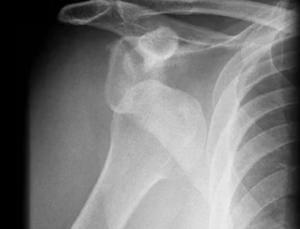

Luxação do Ombro

No ombro, a luxação geralmente ocorre por trauma indireto, ou seja, o impacto em outra região do membro superior faz com que o ombro saia do lugar. O tipo de luxação mais comum é a anterior, quando o ombro “sai” para frente, e ocorre quando há queda com o braço esticado. O mecanismo clássico de defesa de quedas.